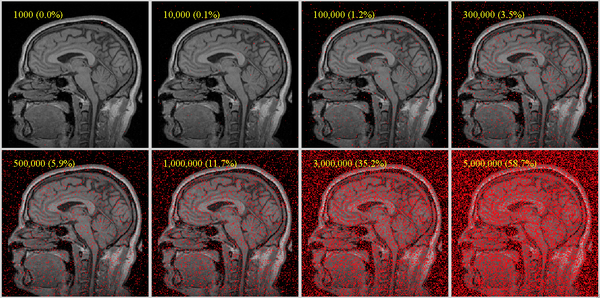

The image below shows sample point densities on one slice of a brain MRI with 256x256x130 voxels. For robust registration, we recommend a useful coverage requires at least 1% coverage for affine, more (at least 5%) for nonrigid (BSpline) as DOF increase: